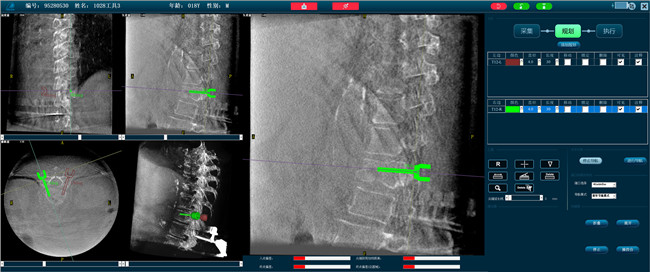

借助骨科機(jī)器人的規(guī)劃軟件進(jìn)行術(shù)前手術(shù)路徑模擬規(guī)劃,找到穿刺位置和角度,操作機(jī)械臂快速完成手術(shù)入點(diǎn)的準(zhǔn)確定位。

*術(shù)前規(guī)劃

步驟二:手術(shù)實(shí)施

在病人體表切開一個(gè)長1-2cm的創(chuàng)口,沿骨科機(jī)器人的機(jī)械臂定位點(diǎn)方向?qū)⒖耸厢槍?dǎo)向套筒,通過創(chuàng)口送至病灶椎體處,并沿套筒方向打入克氏針進(jìn)行定位。沿導(dǎo)針插入工作套管,取出導(dǎo)針,完成球囊擴(kuò)張后,通過骨水泥注入器準(zhǔn)確地在骨折部位緩慢注入骨水泥,幫助其恢復(fù)椎體的形狀和強(qiáng)度。